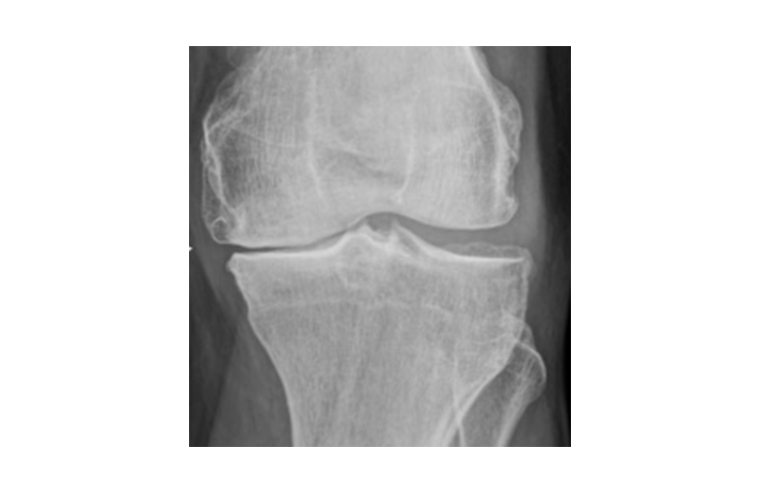

The conservative management of knee osteoarthritis remains a major challenge for clinicians, particularly in young and active patients. Among emerging approaches, injections of platelet-rich plasma (PRP) and autologous fat therapy derived from adipose tissue are generating increasing interest. While PRP has shown moderate chondroprotective effects, the addition of mesenchymal cells from autologous fat therapy may enhance both biological and clinical outcomes, particularly in terms of cartilage regeneration.

The SPOST study (Stromal Vascular Fraction and Platelet-Rich Plasma for Osteoarthritis Study), currently being initiated, is a multicenter, triple-blind randomized controlled trial. We recently published a research protocol aimed at comparing the functional and structural efficacy of a combined autologous fat therapy + PRP treatment versus PRP alone in 108 patients with symptomatic, non-surgical knee osteoarthritis.

Beyond the protocol, our preliminary clinical experience supports the relevance of this treatment. To date, approximately twenty patients have been treated, including several elite athletes. We present here the case of a professional football player with a complete trochlear chondral lesion. Eight months after a combined autologous fat therapy + PRP injection, over 50% regression of the cartilage defect was observed on follow-up arthro-CT, along with a full return to professional-level football, completely asymptomatic.

Although long-term data are still lacking to definitively confirm true cartilage healing, the functional outcomes in our cohort are highly encouraging. This work aims to provide more objective insights into the true potential of combined cell therapy in the treatment of chondropathy and knee osteoarthritis.